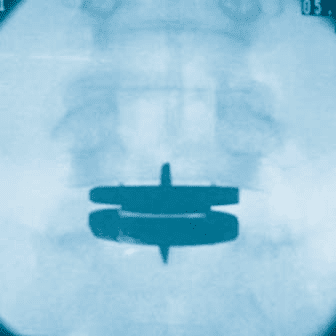

prodisc L Gallery

Click to enlarge image